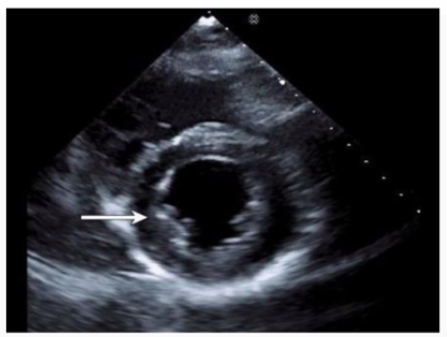

Which wall is indicated by the arrow on this image?

The echocardiographic image is a parasternal long axis or apical view showing the left ventricle. The arrow points to the wall segment located inferiorly, corresponding to the inferior wall of the left ventricle. The inferior wall is typically visualized in parasternal long axis and apical views as the posterior aspect of the ventricle.

Other options correspond to different walls: anterior is anterior septal wall, anterolateral and inferolateral refer to the lateral wall regions. Accurate wall identification is critical for regional wall motion analysis and coronary artery territory correlation.

This segmental wall identification is detailed in adult echocardiography and ASE chamber quantification guidelines12:ASE Chamber Quantification Guidelinesp.90-9516:Textbook of Clinical Echocardiography, 6ep.140-145.